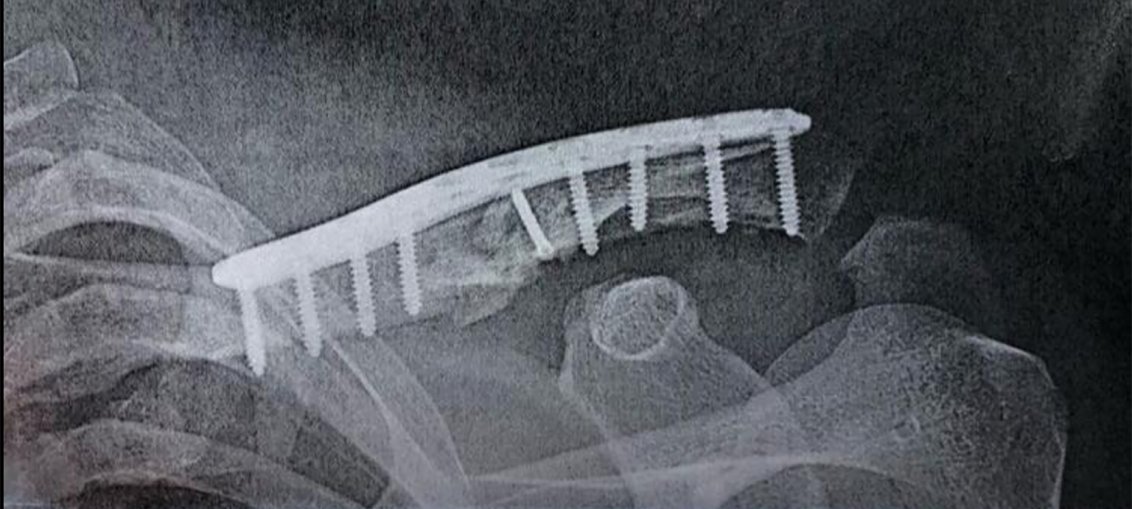

Tommy Searle has had successful surgery on the collarbone he broke in the first corner of the Dutch GP on Sunday. He says he’ll be out for around four weeks, so will miss the opening British championship and the Spanish GP, at least.

He said: “I got caught up in a crash yesterday off the start after a rider went down in front of me and i couldn’t avoid his bike. I had surgery last night to fix my collar bone thats the only injury I had so I’m now on the mend.. It will be about 4 weeks I would think. Not ideal but had far worse. Will keep working hard as I was feeling good.”